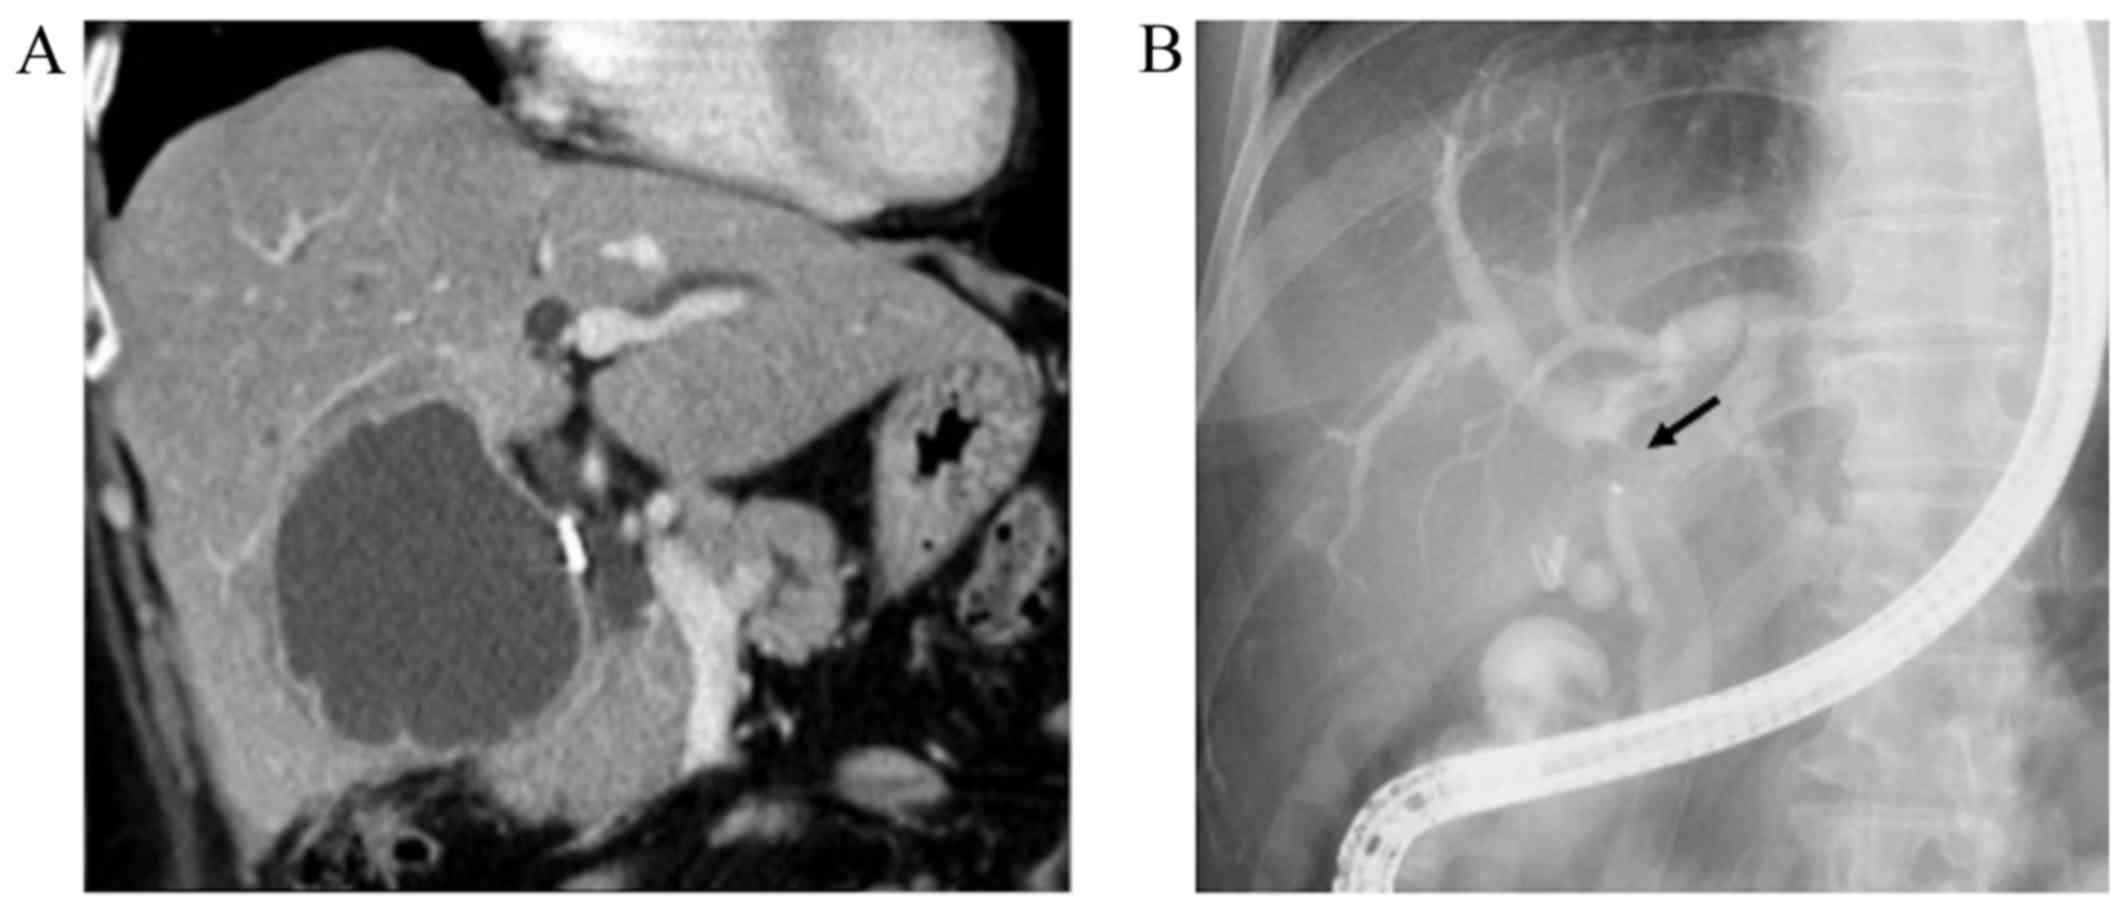

Twenty-six months later, the patient underwent a follow-up CT, which revealed no recurrence in the left hepatic duct, but detected a papillary tumor in the common bile duct (Fig. 4A). On ERC, the tumor appeared to be a mucin-producing neoplasm with abundant mucus secreted from the dilated ampulla of Vater (Fig. 4B). Pancreatoduodenectomy was thus performed for suspected recurrent IPNB. In the resected specimen, the tumor was located in the lower common bile duct (Fig. 5). The histological appearance of the tumor was nearly identical to that of the original neoplasm, with a similar immunohistochemical phenotype (Fig. 5). No invasive cancer was found. The tumor was surrounded by non-neoplastic epithelium. The postoperative course was uneventful, with no signs of recurrence at the time of writing of this manuscript (follow-up of 12 months).

Figure 4.

Contrast-enhanced computed tomography (CT) and endoscopic retrograde cholangiopancreatography showing a recurrent intraductal papillary neoplasm of the bile duct. (A) Contrast-enhanced CT (coronal image) showing a mass lesion in the distal bile duct (arrow). (B) The orifice of the ampulla of Vater is dilated with mucus secretion.